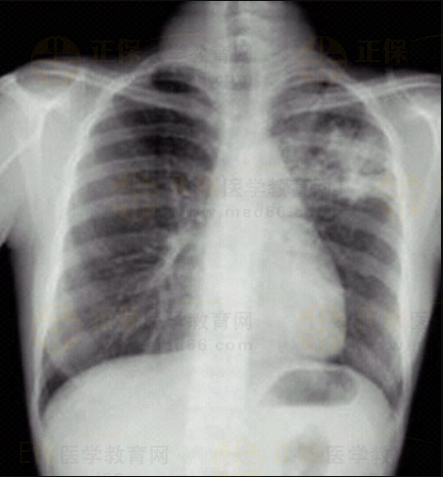

03卷-3.病史:男性,34歲,咳嗽、無痰半月,伴低熱。診斷。

A.左上支氣管擴(kuò)張

B.左上肺炎

C.左上浸潤型肺結(jié)核

D.左側(cè)胸腔積液

【該題針對(duì)“ X線-浸潤型肺結(jié)核 ”知識(shí)點(diǎn)進(jìn)行考核】